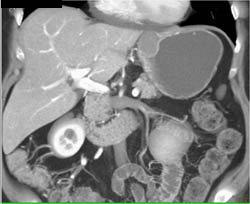

GIST Tumor With Ulceration